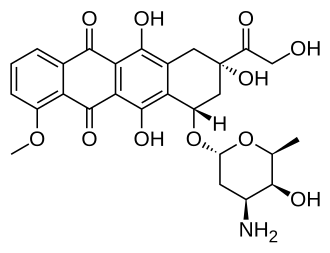

| Formula | C27H29NO11 |

| Molar mass | 543.525 g·mol−1 |

Doxorubicin (DXR) is a 14-hydroxylated version of daunorubicin, the immediate precursor of DXR in its biosynthetic pathway.

The planar aromatic chromophore portion of the molecule intercalates between two base pairs of the DNA, while the six-membered daunosamine sugar sits in the minor groove and interacts with flanking base pairs immediately adjacent to the intercalation site, as evidenced by several crystal structures.[39][43]